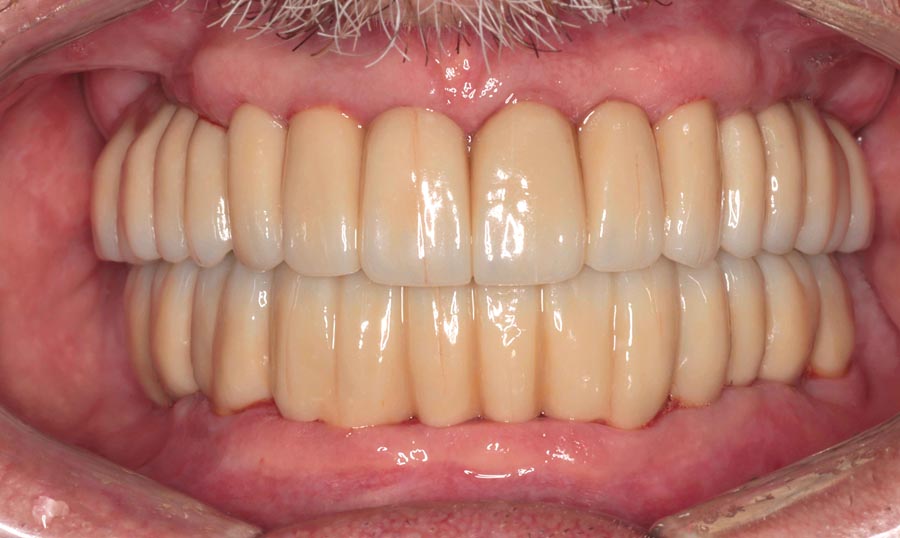

Smile GalleryImplant RestorationsFull Mouth Implant Restoration 1 of 13 Pre-operative smile Pre-operative smile Pre-operative frontal view, lips retracted Pre-operative panoramic image (note bone levels) Post-surgical panoramic image Surgical temporary bridge (note convex contours) Delivery of surgical temporary bridges in both upper and lower Two weeks post-op surgery and temporaries (note amazing tissue response) Three months post- surgery. (Note tissue development) Definitive implant bridges (FP-2) Post-treatment panoramic image Final result smile Final result smile